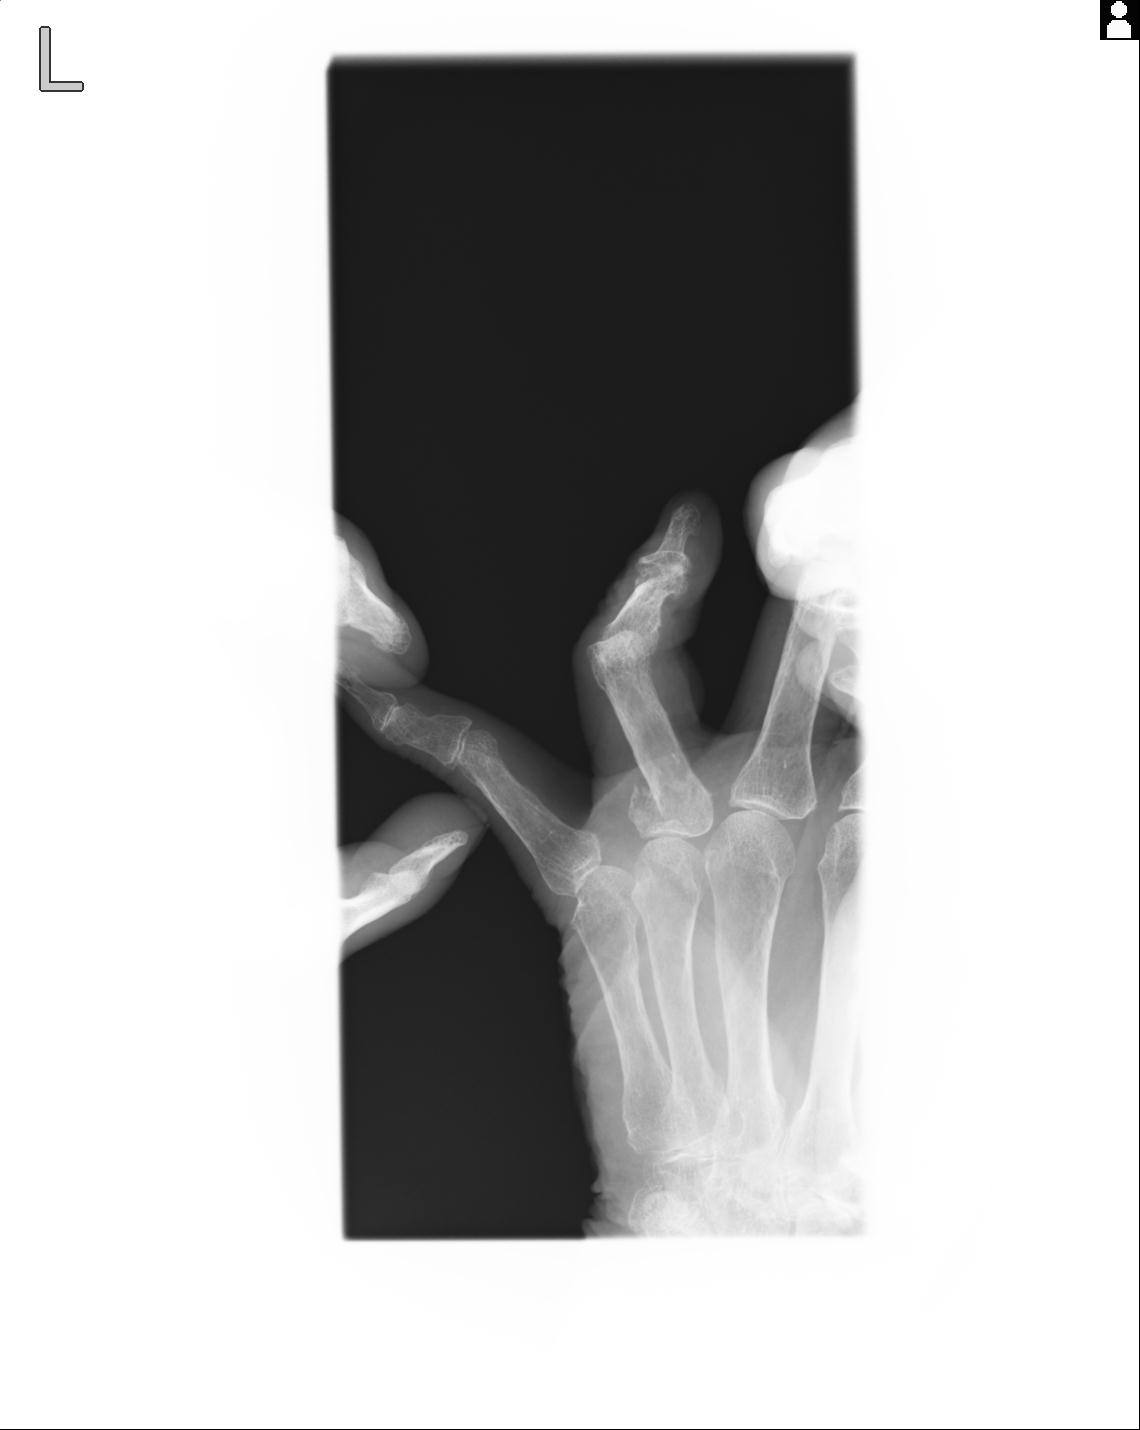

102860 1/21 (4R) 1/26 (4R) 3/15 左手 2R 91歳女性 左環指中節骨